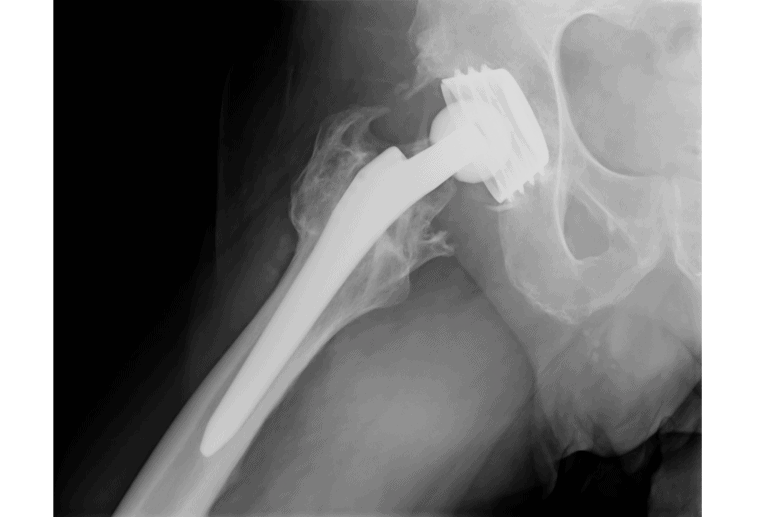

Hüftgelenkenendoprothese / Hüftprothese

Eine Hüftgelenksendoprothese, oft einfach als Hüftprothese bezeichnet, ist ein künstlicher Gelenkersatz, der dazu dient, ein verschlissenes oder beschädigtes Hüftgelenk zu ersetzen. Die Hüftprothese besteht in der Regel aus Metall, Keramik und/oder Kunststoffkomponenten und imitiert die Funktion des natürlichen Hüftgelenks.

Die Vorteile einer Hüftgelenksendoprothese sind:

- Schmerzlinderung: Eine der Hauptindikationen für eine Hüftprothese ist anhaltender, durch Arthrose verursachter Schmerz, der durch konservative Maßnahmen nicht gelindert werden kann. Nach dem Eingriff erleben viele Patienten eine signifikante oder sogar vollständige Schmerzlinderung.

- Wiederherstellung der Mobilität durch ein künstliches Hüftgelenk.

- Verbesserung der Lebensqualität durch die Verringerung der Schmerzen und die Erhöhung der Mobilität.

- Langlebigkeit: Moderne Hüftprothesen sind auf Langlebigkeit ausgelegt und können viele Jahre, oft sogar Jahrzehnte, halten.

- Erfolgsrate: Die Operation zur Implantation einer Hüftprothese hat eine hohe Erfolgsrate und zählt zu den erfolgreichsten chirurgischen Eingriffen in der Orthopädie.

Minimalinvasive Operation der Hüftprothese

Die Implantation eines künstlichen Hüftgelenks durch minimalinvasive Techniken bietet Patientinnen und Patienten zahlreiche Vorteile, da der minimalinvasive Eingriff besonders gewebeschonend ist. Weitere Vorteile sind beschleunigte Wundheilung, vollständiger Krafterhalt, unauffällige Narben und ein reduziertes Risiko für postoperative Komplikationen.